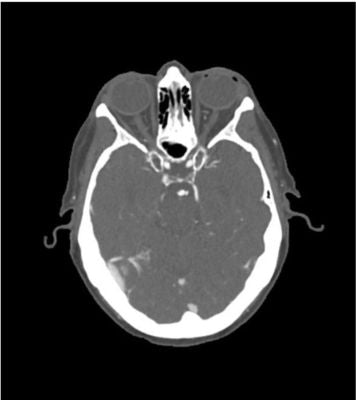

This phantom simulates a contrast medium enhanced head in arterial phase (CT angiography). It covers the vertex to the foramen magnum.

The phantom has three intracranial aneurysms of the middle cerebral artery (MCA), anterior communicating artery (ACoA), and the basilar artery.

The phantom can be used in CT (including CBCT) to evaluate and optimize imaging performance and AI-enabled diagnosis. It is also suited for training purposes.

The phantom provides a detailed and realistic simulation of common brain pathologies, soft and bone tissues. Air voids are filled with a cellulose-polymer composite of approx. -160 HU.

Diagnostic features - Aneurysms:

• Middle cerebral artery (MCA)left side

• Anterior communicating artery (ACoA)left side

• Basilar artery left side